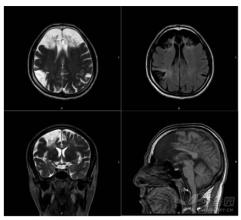

脑炎后遗症影像图